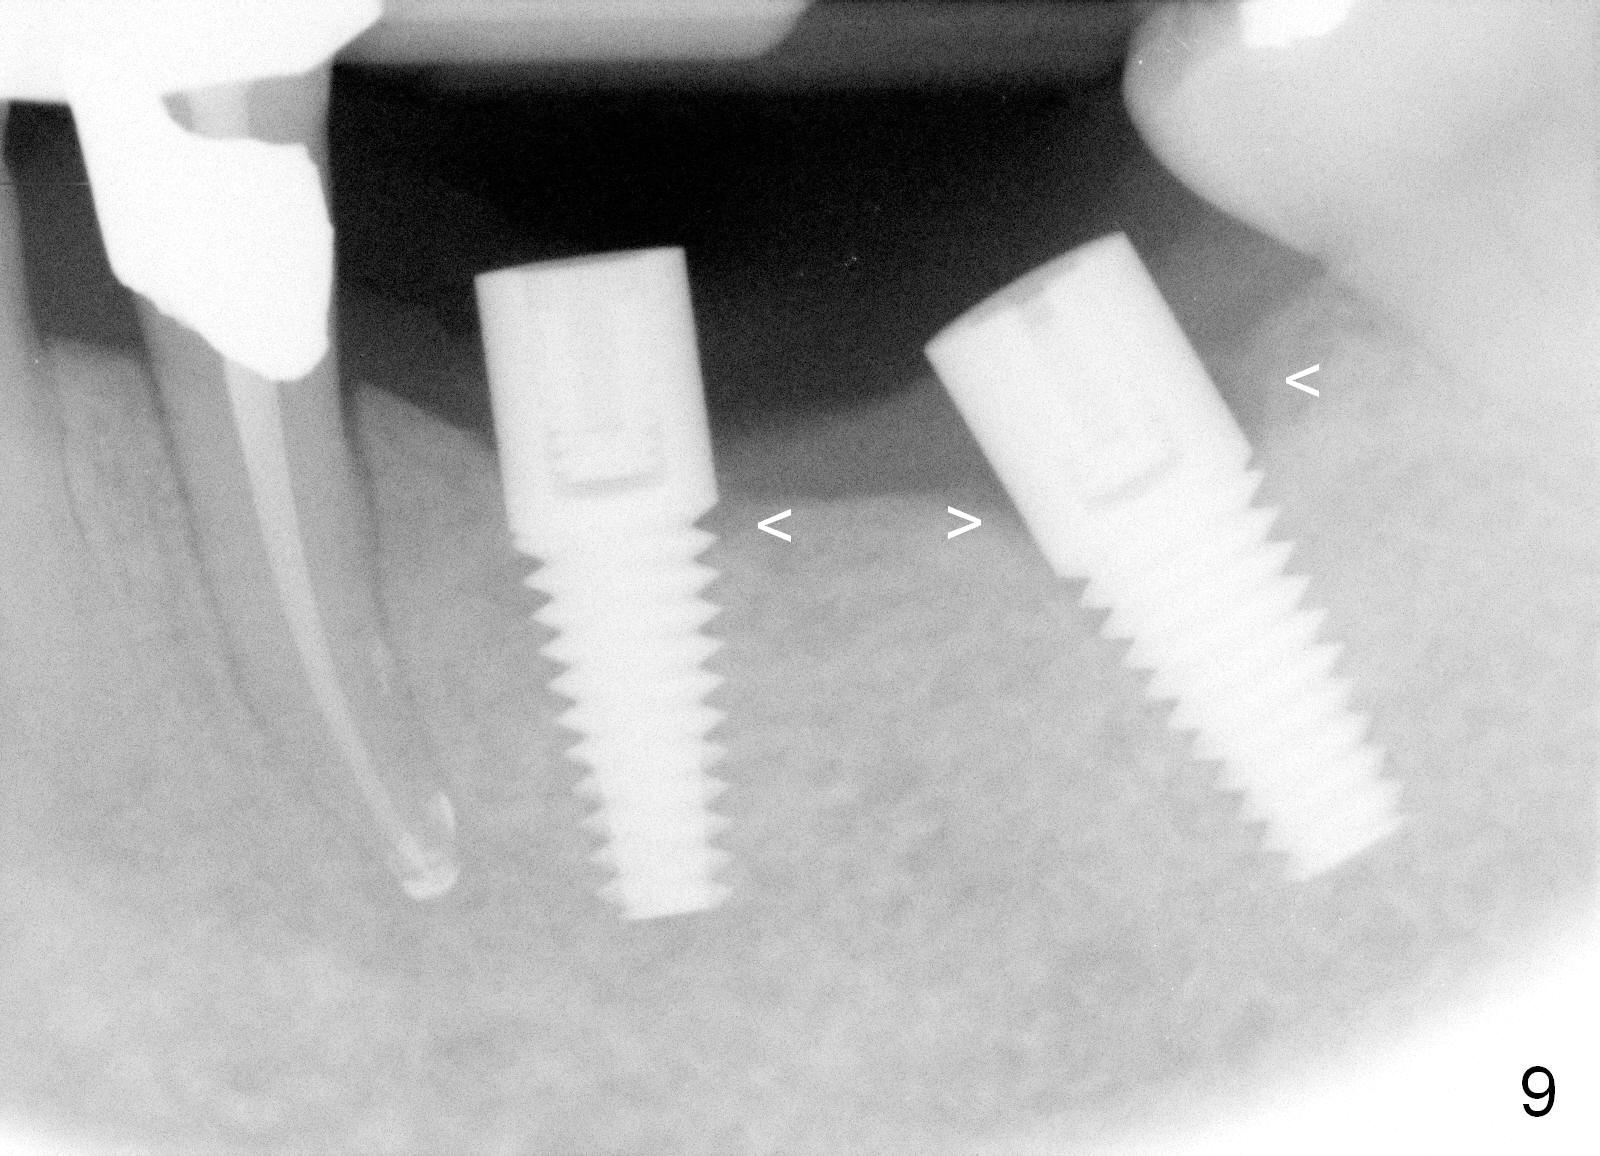

Three months postop, crestal bone has started to resorb (Fig.9 arrowheads). Resorption gets worse over time (Fig.10: 4 months post cementation, 11 months postop) (Fig.11: 1 year 2 month post cementation). On the other side (#30), postop bone resorption is not so severe. The patient's main concern is that she does not have normal taste ever since she got the implants.